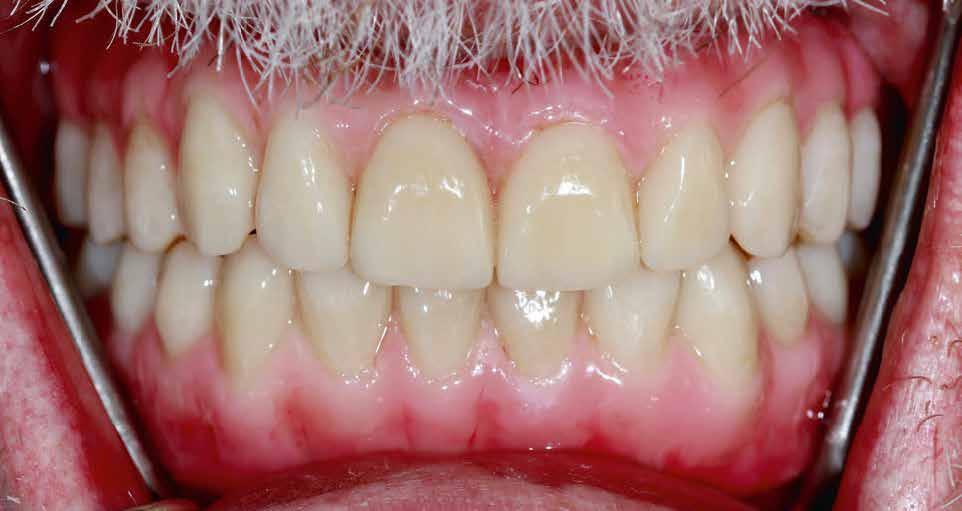

Próba és behelyezés

A felépítmény próbája és behelyezése a szájba a segédelemmel történik. Az emergenciaprofil kezdetben még

enyhén anémiás (vérszegény – a ford.), de gyorsan újra telítődik, tökéletesen illeszkedve a szituációhoz (36–42. képek)

A páciens a DD cube One koronát választotta, ami szín és transzparencia szempontjából is nagyon harmonikusan illeszkedett a teljes képhez (43–44. képek)